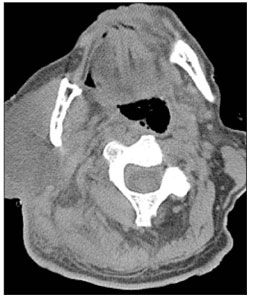

Empiric therapy that is active against S aureus is first-line treatment, although secretions from the gland should be obtained and cultured to rule out infection by other organisms, including streptococci, gram-negative and anaerobic organisms, and MRSA. Interventions, such as gland massage, may be needed to facilitate drainage of an infected Stensen duct. A CT scan or an ultrasonogram may be required to confirm diagnosis (Figure 8), especially in patients who are unresponsive to therapy within the first 72 hours. Depending on the results of imaging studies-such as identification of complicated infection-surgical intervention may be required.

Figure 8 –A CT scan of the head of the patient shown in Figure 7 reveals diffuse swelling and inflammation of the right parotid gland. The inflammation is seen infiltrating the surrounding muscle and fat planes and extending toward the region of the carotid sheath. (Photo courtesy of Andrew Koon, MD, Andrew Bagg, MD, Kevin O’Brien, MD, and Carrie Vey, MD. Overview adapted from Photoclinic in Consultant. 2006;46:1405-1406.)